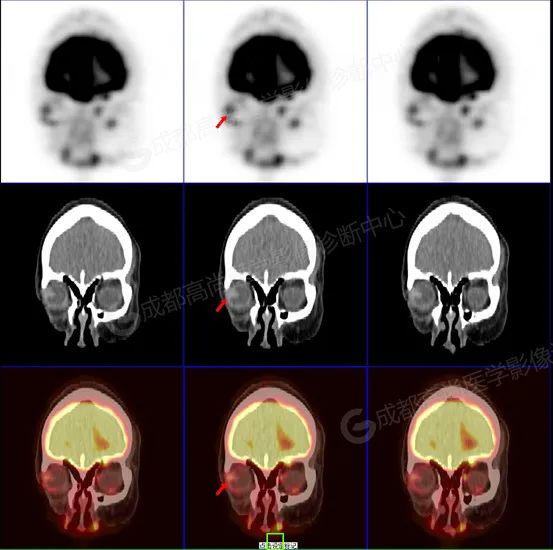

图 1-3 检查所见:紧贴右侧眼球外侧壁类三角形高密度结节突入玻璃体内(大小约 1.0 cm×1.1 cm×1.2 cm),邻近外侧和后侧眼环轻度增厚,FDG 代谢轻度增高,提示多为恶性肿瘤性病变,请结合病理。

脉络膜黑色素瘤病灶多见于眼球后壁及颞侧壁, 以隆起性形态 (半球形、蕈状、结节状) 为主。有较高的隆起高度,具有特征性 T1WI 高、T2WI 低信号,增强有强化。18-F FDG 显像均匀不同程度代谢增高,全身其余部位未见确切原发病变。